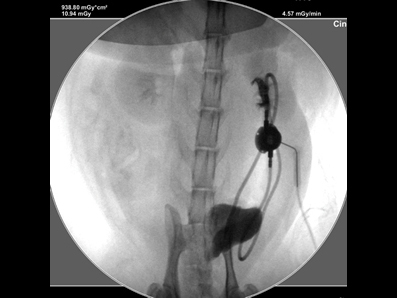

造影で漏れがないか何度も確認

必ず透視下にて漏れがないか何度も確認をします。 透視をしないとシステムや装着部分からの漏れが確認されたり、トラブルが考えられます。

透視下にて実施すれば適切な位置に装着できます。

透視下にて腎盂に入っていることを確認。

ここにカテーテルを装着していきます。

SUBシステムを設置しました。

漏れを確認して終了となりました。